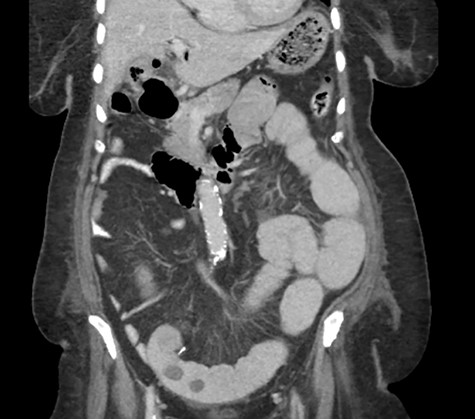

Postoperative course was marked by a slow recovery evidences by persistently high nasogastric tube output and failure to open her bowel. On the third postoperative day, a trial of therapeutic Gastrografin was given, not much improvement was achieved, and the patient continued to be obstructed. A repeat abdominal CT scan was obtained on day 5 due to persistence of intestinal obstruction. It showed dilated contrast-filled small bowel loops with multiple filling defects, indicating recurrent GSI (Fig. 4).

A CT abdomen and pelvis scan showing multiple large stones in the small bowel.